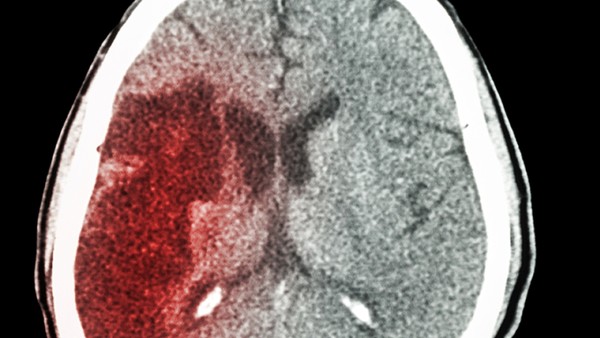

患者脑梗塞后手脚麻木可服用营养神经药物和维生素b1,手麻木和脚麻木是脑梗塞病常见的症状,容易发生丘脑梗塞的患者。另外,患者平时需要进行二次预防,避免脑梗塞的再次发生和脑梗塞的症状越来越严重,饮食清爽易消化,最好不要吃辛辣油腻的食物。特别是夜间睡眠时间充足,尽量保持在8~10小时,在生活中养成早睡早起的好习惯。

1、患者脑梗塞后手脚麻木,血管狭窄引起的脑细胞局部缺血、坏死等,必须立即服用营养脑细胞的药物。